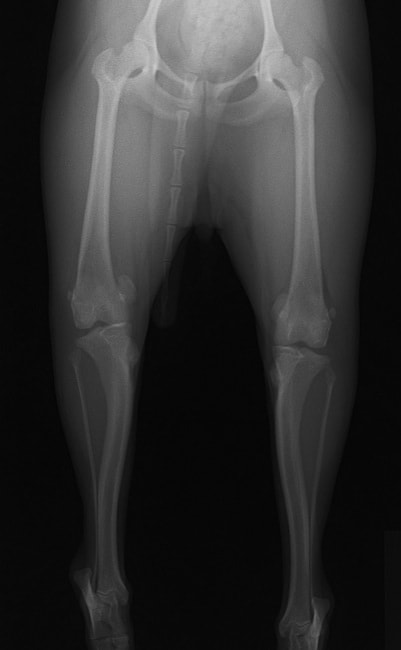

■ 症例24 キャバリア 7か月

左右膝蓋骨内方脱臼(左:グレードⅣ 右:グレードⅢ)

以前から左右後肢の跛行が認められ、整形外科学的検査・レントゲン検査により左右の膝蓋骨脱臼が認められた。症状が重度である左膝の膝蓋骨脱臼整復術を行った。外科手技は縫工筋及び内側広筋の解放、脛骨粗面の外側転位、滑車ブロック形造溝術、内外側関節方の縫縮を実施した。術後一か月時点で、左の膝蓋骨は安定しており経過は良好である。

本症例は成長期における重度の膝蓋骨脱臼であり、術後の再発の可能性もあるため、経過をしっかりと観察していく必要がある。また、今回手術を実施していない右膝に関しても経過を観察し、手術を検討していくこととする。